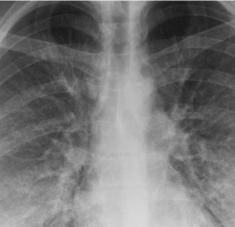

La edad aparente basada en la radiografía de tórax puede reflejar con precisión las condiciones de salud más allá de la edad cronológica (The New York Times).